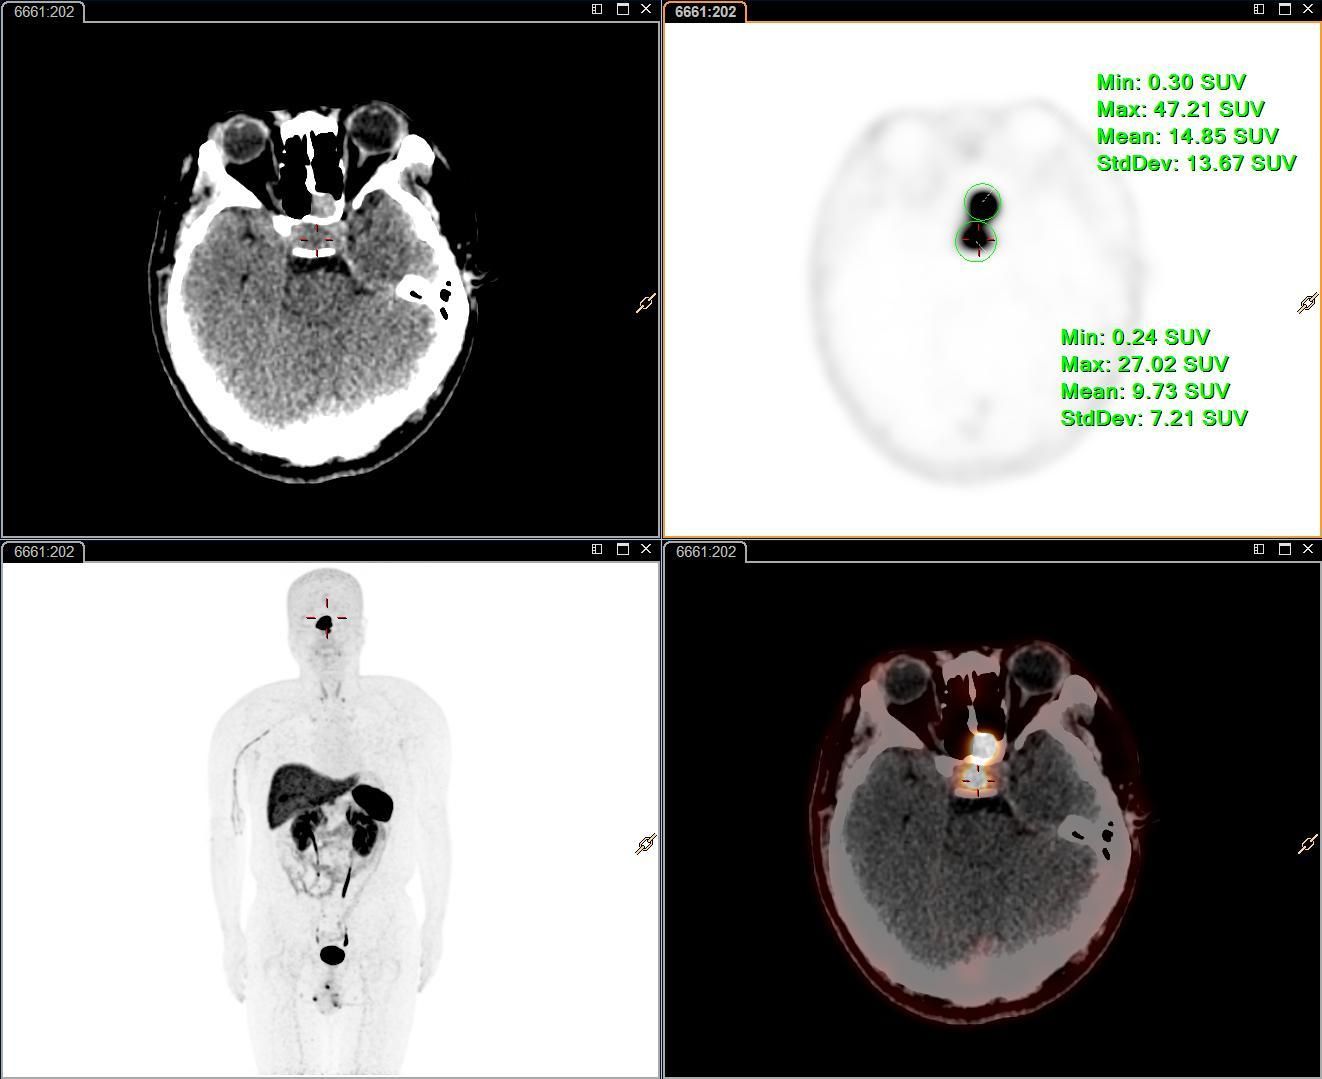

近日,核医学科成功开展了我院首例奥曲肽PET/CT神经内分泌肿瘤显像检查,为神经内分泌肿瘤的早期诊断、精准分期、疗效评估提供了全新的解决方案,标志着我院在肿瘤分子影像诊疗领域的新征程。

本次显像病例是一位24岁的年轻男性患者,因左侧鼻塞活检提示神经内分泌肿瘤(NET,G2),免疫组化提示SSTR2(3+),患者行治疗前评估。核医学科团队在充分告知并取得知情同意后,为该患者进行18F-奥曲肽PET/CT显像。结果显示,18F-奥曲肽 PET/CT能明显显示病灶范围,充分体现了18F-奥曲肽PET/CT在神经内分泌肿瘤诊疗中的优势。